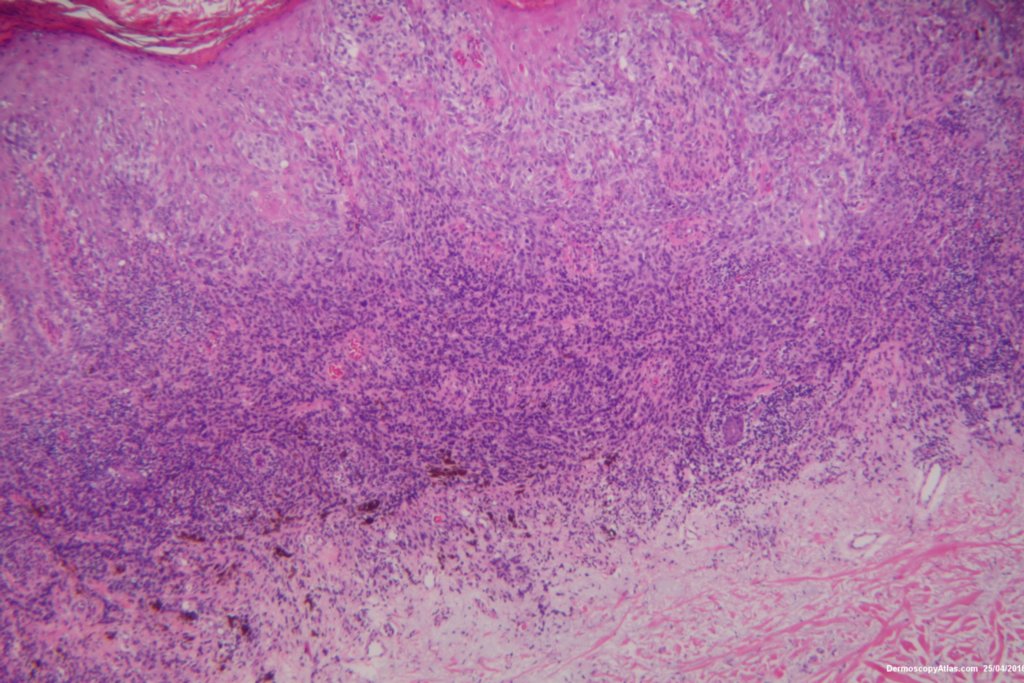

The shave biopsy was reported as a level 4 Invasive melanoma 1.7 mm thick with 3 mitoses per high powered field. There were no groin glands enlarged clinically.